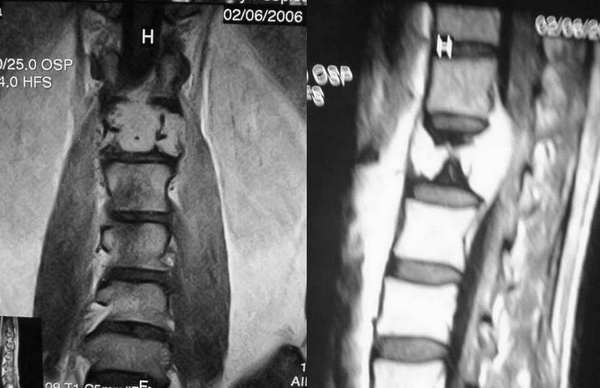

增强图像显示不清,好像有肺门及纵隔与腋下淋巴结肿大,右侧胸腔积液,腰1椎体骨质破坏,椎旁软组织肿块形成,其后硬脊膜囊明显受压。考虑淋巴瘤可能。其他待排。

腰椎骨质破坏,但未侵及椎间盘,椎前软组织肿胀,考虑腰椎转移瘤可能

腰椎骨质破坏,但未侵及椎间盘考虑腰椎转移瘤可能

请问腰椎ct有没有平扫的,有没有骨窗位的,怎么在mri上有条片状信号缺失区,所以,结合平片我认为椎体血管瘤也无法排除????